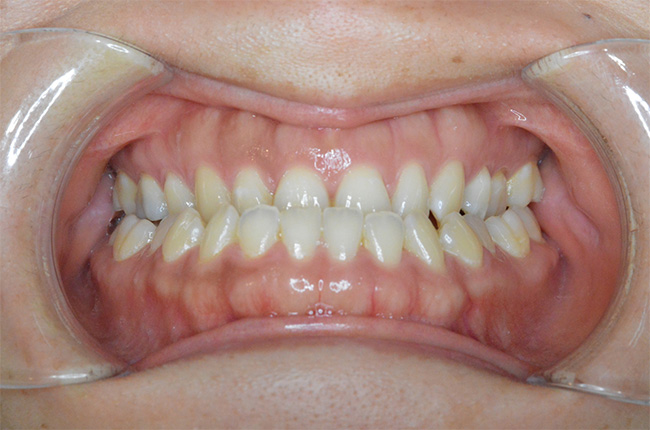

治療開始時